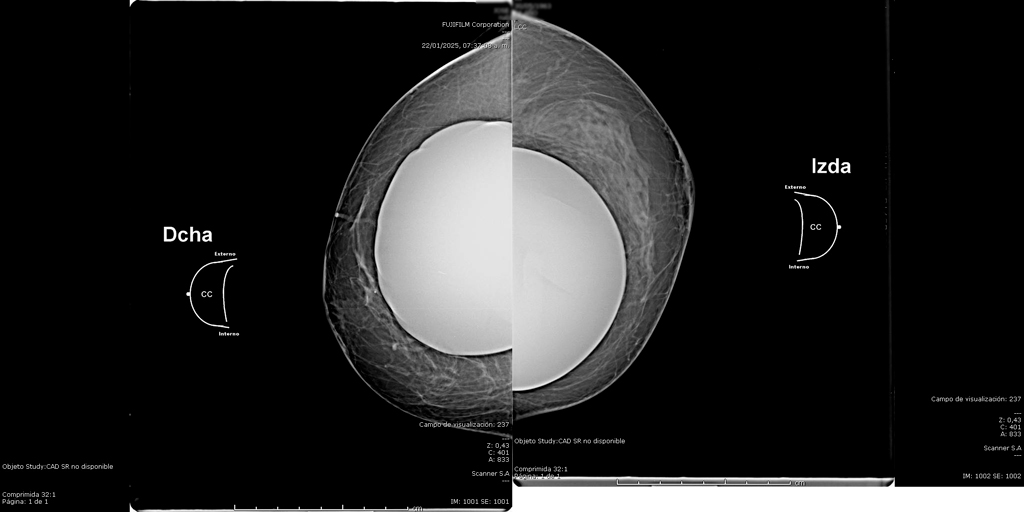

La mamografía es un estudio de diagnóstico por imagen que utiliza bajas dosis de rayos X para obtener imágenes detalladas del tejido mamario. Es una herramienta fundamental para la detección temprana del cáncer de mama y otras patologías mamarias, incluso antes de que sean evidentes al tacto o generen síntomas. Su uso regular en controles preventivos permite salvar vidas al facilitar diagnósticos oportunos y tratamientos más efectivos.

En SCANNER S.A, nuestros equipos digitalizados permiten detectar cambios mínimos en el tejido mamario con alta claridad, permitiendo asi tener un diagnostico preciso y entregar unos resultados reales a nuestros pacientes.